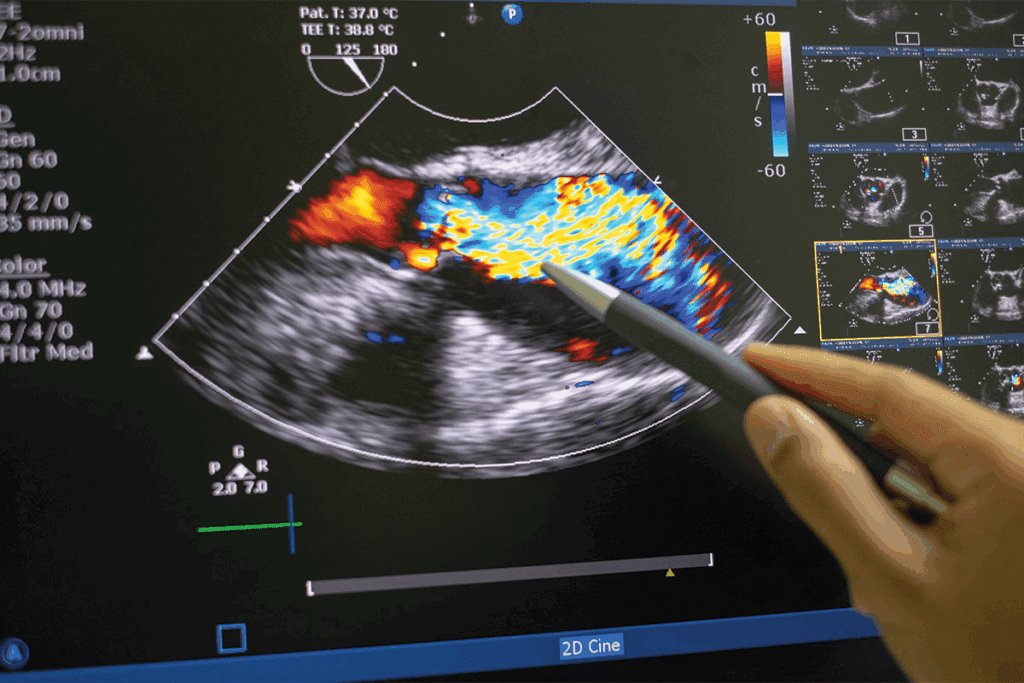

Doppler Imaging in Adenomyosis

Adding color Doppler to ultrasound makes it even better. It shows us the uterus’s structure and blood flow. Doppler imaging is great for spotting vascular changes in adenomyosis.

This helps doctors tell adenomyosis apart from other conditions. It also shows how severe the disease is.